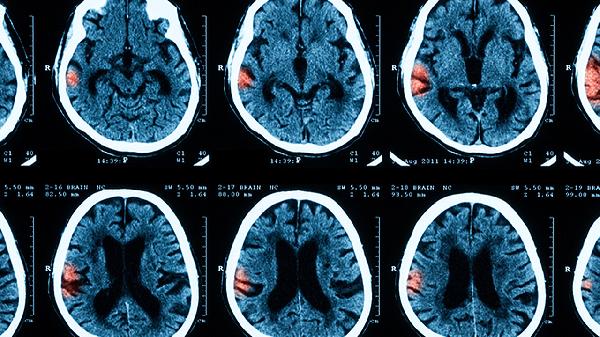

先天性脑膜炎患儿在出院后需要定期做脑电图和头部影像学检查,避免剧烈活动和感染诱发病情复发。饮食上应保证足够的蛋白质和必需脂肪酸,比如深海鱼、核桃等有助于大脑健康的食物。还可以适当参与水疗、音乐疗法等感官刺激活动。家庭成员应学习基本的护理知识。疫苗接种方案需根据孩子的免疫状况调整,若接触过感染者,应及时使用预防性药物。心理支持应在整个成长过程中持续提供,帮助孩子更好地适应社会生活。